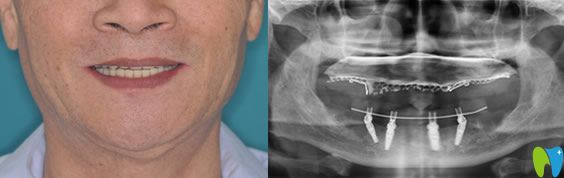

口腔情況:全口牙缺失;

種植方案:佛山智媄口腔醫(yī)生對林大爺?shù)目谇缓脱啦酃乔闆r進(jìn)行了自信的分析,建議采用all-on-4全口種植技術(shù)。

All-on-4種植技術(shù):是歐美全新的種植牙技術(shù),也是非常適合半口及全口牙缺失的修復(fù)方法。僅需植入4顆人工牙根,就能將半口牙固定,一次完成,痛苦小,而且種植后的牙齒當(dāng)天就可以吃東西,能真正的做到即種即用。

林大爺做種植牙后感言:一直覺得像自己的情況需要種10幾顆牙呢,沒想到僅僅種了4顆種植體就“長出”了一排牙齒。而且在整個種植過程中沒有感覺到疼痛,醫(yī)生手法很輕,術(shù)后出血也很少,真的很意外我這么大年紀(jì)的人了,也恢復(fù)的很快,現(xiàn)在的牙齒可好用了,像年輕時的真牙一樣,終于能吃肉了!